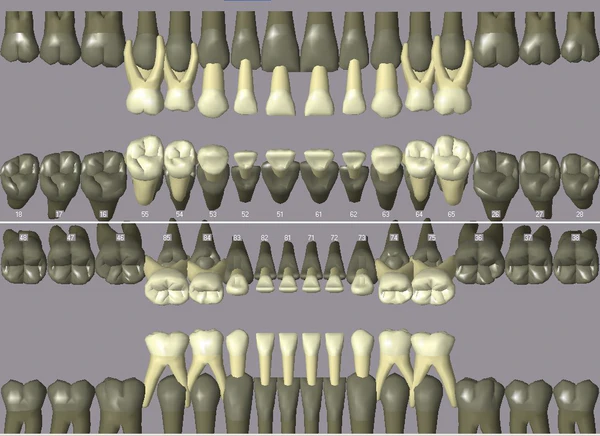

Первый зуб-моховик появляется у ребенка на шестом месяце жизни. К трем годам прорезываются почти все молочные зубы. В шесть лет молочные зубы начинают замещаться первыми постоянными зубами, заканчивается их замена к тринадцати годам. Четыре коренных зуба (зубы мудрости) обычно появляются после 18 лет.

У взрослого человека имеется от 28 до 32 постоянных зубов (8 резцов, 4 клыка, 8 малых коренных и 8-12 больших коренных). Состав зубов принято выражать зубной формулой: -- 2 резца, 1 клык, 2 малых и 3 больших коренных зуба.